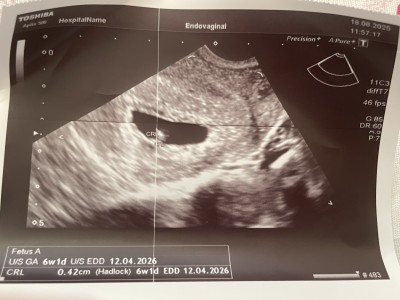

Adete göre 9+2 haftalık hamileyim ama 3.hamileliğim hep geç döllenme oluyor doktor bugün kalp sesi için çağırmıştı tahminen 7 haftalık olacaktı kendi doktorum kalp sesi yok artık duymamız lazımdı sağlıksız bebek gebeliği sonlandırmak gerekir dedi ordan çıkıp farklı doktora gittim o da kalp sesi az ultrasona göre 6+1 kese bebek sağlıklı gözüküyor 1 hafta daha bekleyelim dedi sağlıksızsa kalbi ya tamamen durur ya da ses daha netleşir dedi tabi ki ben beklicem çünkü kızım da 3 hafta kadar geç döllenmeydi doktor adet tarihini değiştirmişti sizce duyulur mu bu durumu yaşayan varmı

Gebelik haftası 9+2